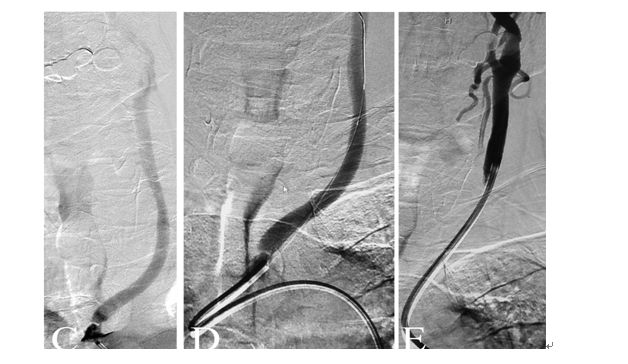

全麻下,血管造影显示右侧颈内动脉起始段完全闭塞,同侧眼动脉逆行充盈右侧颈内动脉,向近端反流到海绵窦上段同3月前的造影

先行颈动脉近端闭塞处切开并行内膜剥脱,再切口处置入动脉鞘后,用300cm 0.014微导丝交换出微导管用1.5mm×20mm gateway 行闭塞段扩张,造影显示右侧颈动脉闭塞段通畅

再使用3mm×20mm球囊行从上往下预扩张C2段三次,扩张后置入ENTERPRISE 支架4.5mm×28mm自膨支架两枚,经股动脉造影显示颈动脉全程完全畅通。复查CT未见新发梗死灶。